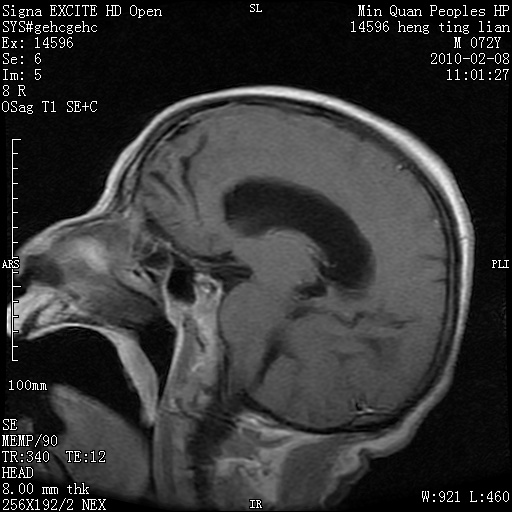

m,72,头疼,头晕两年,伴视力模糊三月,饮食呛咳两天。pe:颈部抵抗,左眼突出,左眼瞳孔约3mm,对光反射消失,双眼失明,伸舌困难,双肺呼吸音粗,心率110次/分,左上肢肌力i级,左下肢屈曲,肌张力高。现有08年2月19mri平扫及10年2月8日mri增强请会诊。ct病灶呈低密度伴散在点、片状等密度区,无明确钙化(无ct片资料可供上传)。[

左侧桥小脑区占位伴梗阻性脑积水----考虑 1神经鞘瘤 2室管膜瘤。

左侧桥小脑区神经鞘瘤伴梗阻性脑积水。

左侧桥脑小脑角区肿瘤并脑积水,考虑听神经瘤,脑膜瘤?

左侧桥脑小脑角区肿瘤并脑积水,考虑听神经瘤,